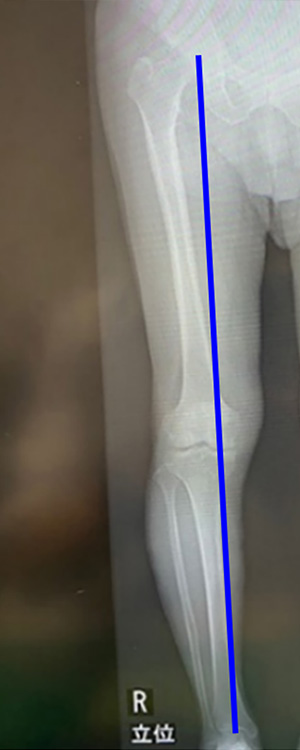

画像

左:荷重線が膝の内側の痛い部位を通る

中:O脚をイラストにするとこのような荷重線がかかっている

右:斜線部が足底版。外側が高い足底版(インソール)を履くと拇趾側に体重が寄って、結果として荷重線は膝の内側から離れる。痛みが出にくくなる。

画像元:

写真   筆者撮影

イラスト 高岡整志会病院

変形性膝関節症では、膝の内側に痛みが出やすく、O脚により体重が膝の内側へ集中することが原因です。

体重の負荷がかかる軌道を「ミクリッツライン」といい、これが膝の内側を通ると関節への負担が増します。

そこで、足底装具(インソール)を使用し、足に傾斜をつけることで体重の負荷を外側へ分散させ、膝への負担を軽減し痛みを和らげることができます。足の傾斜は、外側(小指側)が高く、内側(親指側)が低いイメージです。